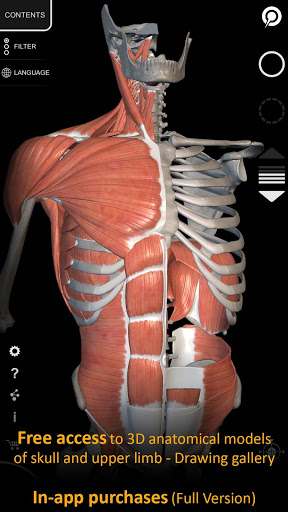

Cette application est téléchargeable gratuitement, mais un achat intégré est nécessaire pour débloquer le contenu.

Le système squelettique complet et quelques autres contenus sont toujours librement accessibles, ce qui vous permet d'essayer l'application correctement.

• Visualisation des muscles à travers des niveaux de couches depuis les plus superficielles jusqu'aux plus profondes

• Les termes anatomiques et l'interface utilisateur sont disponibles en 11 langues : latin, anglais, français, allemand, italien, portugais, turc, russe, espagnol, chinois, japonais et coréen